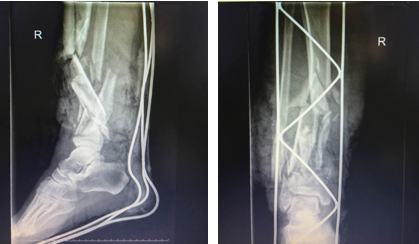

清創(chuàng)、骨折部位固定